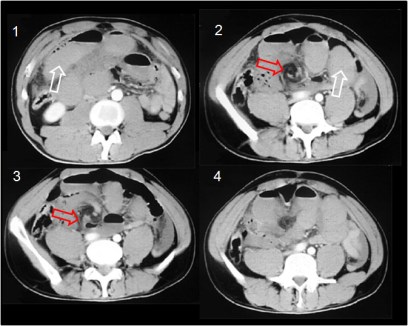

Signo altamente sugerente de vólvulo de intestino delgado, presente en la TC abdominal. Se ve como una imagen de distorsión vascular con vasos y tractos dispuestos en remolino, y ocurre cuando un asa intestinal rota alrededor de un punto fijo de obstrucción provocando la torsión del mesenterio a lo largo del eje de rotación. El signo es más visible cuando el corte es perpendicular al eje de rotación.

La imagen muestra una secuencia de cortes de TC en el mismo paciente. En la imagen 1 se ven asas de intestino delgado dilatadas y rellenas de líquido debido a la obstrucción (flecha blanca). En las imágenes 2, 3 y 4 puede verse el signo del remolino a diferentes alturas (flecha roja). La imagen 3 presenta el asa aferente y el eferente adelgazadas y terminando en “pico”.

Aunque en pacientes con obstrucción por bridas o por hernias internas puede verse una distorsión vascular que parece un remolino, en estos casos no suele alcanzarse un giro completo de 360 grados que caracteriza al vólvulo de intestino delgado.